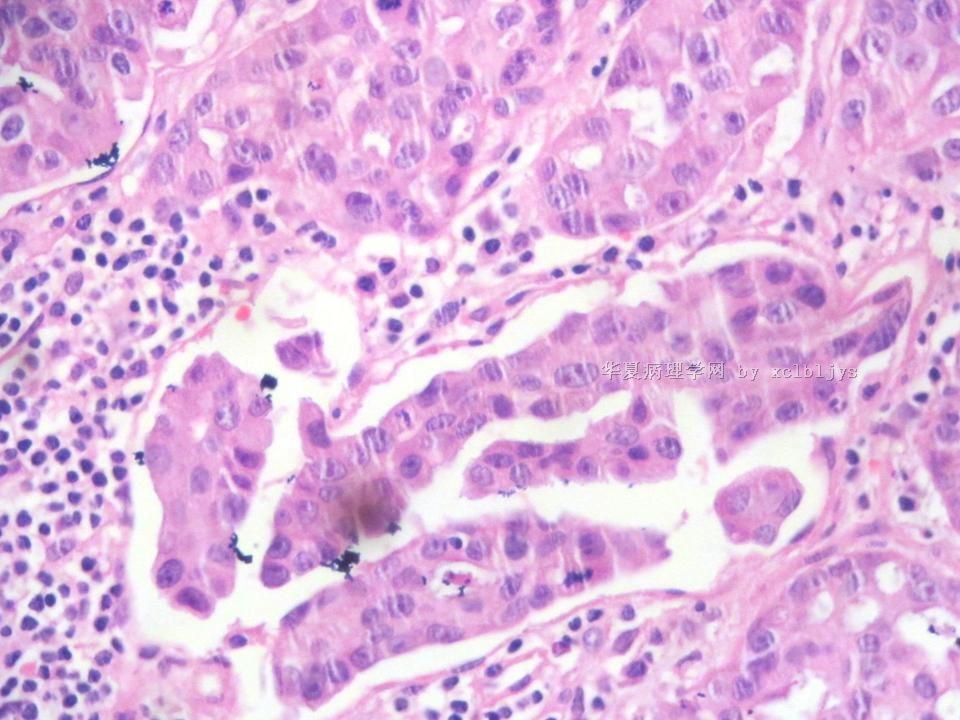

姓    名: ××× 性别:  男 年龄:  56

左锁骨上肿块三月余,手术切除。

蚕豆大肿块,包膜较完整,切面灰红色,质软。

• 左锁骨上肿块(IHC)图3

图3

免疫组化结果:TTF-1(+),CK7(+),CK20(-),TG(-)。临床近一步检查,肺未见肿块,左甲状腺发现肿块,目前仍未处理。

从形态结构看,有腺泡也有乳头结构,倾向转移性肺腺癌。